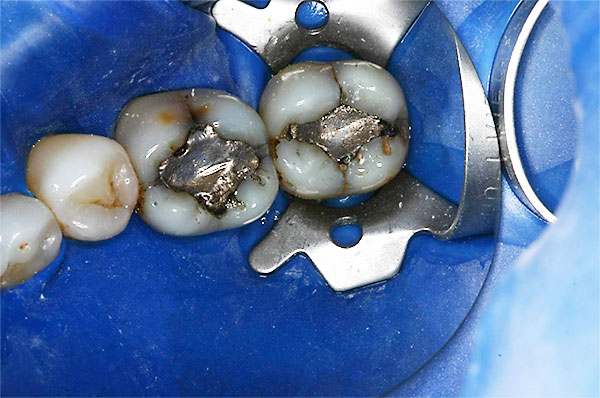

Compositerestauration

![]() |

Zahnärztliche Kunststofffüllmaterialien eignen sich hervorragend für die substanzschonende Versorgung kleiner bis mittelgroßer Defekte am Zahn. Hinsichtlich Härte, Abriebfestigkeit und Stabilität gegenüber Flüssigkeiten (z.B. Speichel) haben sie bessere mechanische Eigenschaften wie Amalgamfüllungen. Bei ausgedehnten Defekten jedoch stoßen die Kunststofffüllungen an die Grenzen ihrer Dichtigkeit und Stabilität. In solchen Fällen ist, je nach Größe der Defekte, Einlagefüllungen wie Keramikinlays, Goldinlays oder Kronen bzw. Teilkronen den Vorrang zu geben.